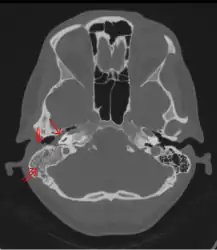

Acute mastoiditis -

CT scan: Otitis media (simple arrow) and mastoiditis (double arrow) of the right side (left side in image). The external auditory canal is partially occupied by suppuration (triple arrow). 44-year-old woman